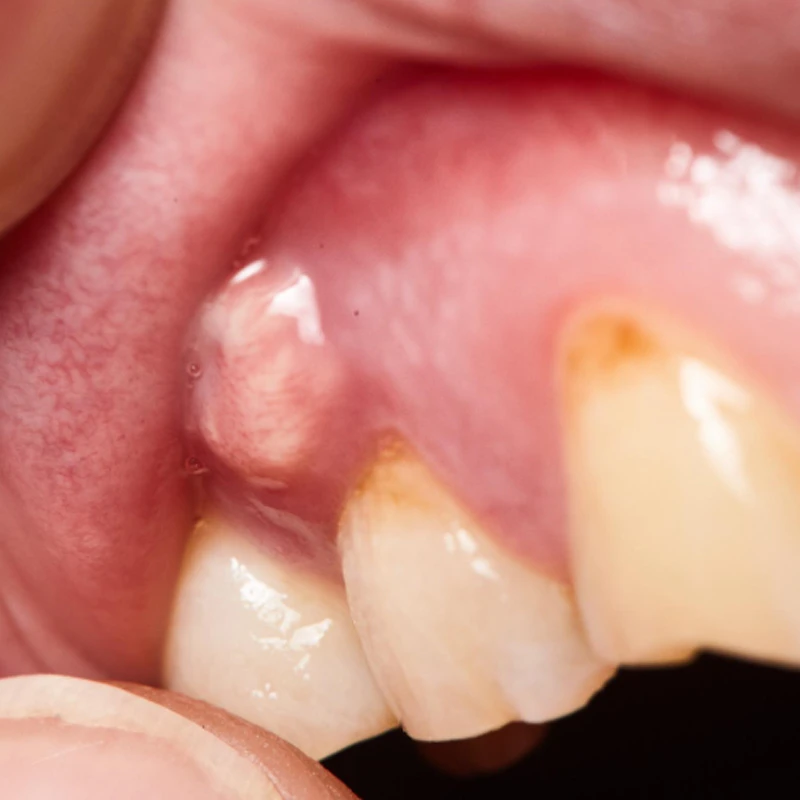

Fibromas

Los fibromas son bultos suaves y redondeados que generalmente se desarrollan por irritación crónica en las encías. Pueden ser causados por factores como el uso de prótesis mal ajustadas o un cepillado dental agresivo.

Bulto en la encía

• Los fibromas suelen ser bultos suaves y redondeados, causados por irritación crónica en las encías.

Bulto, fibroma

• Para los fibromas en las encías, el tratamiento generalmente implica la eliminación del tejido sobrante a través de procedimientos quirúrgicos mínimamente invasivos. Es fundamental seguir las indicaciones del dentista para garantizar una recuperación satisfactoria y prevenir futuras irritaciones.